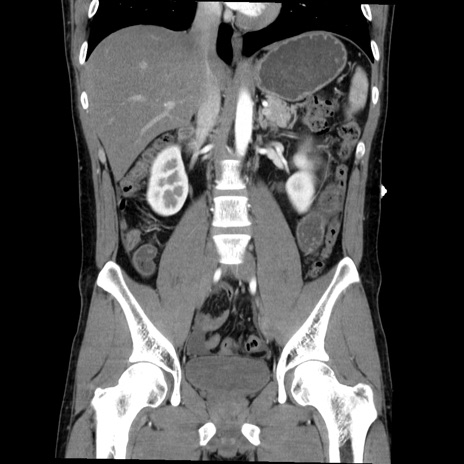

症例36(冠状断像)

【症例】20歳代 男性

【主訴】心窩部痛

【現病歴】今朝より上腹部痛あり。一旦軽快していたが再度出現したため救急要請。昨日夕に白身の魚を含む刺身を食べた。

【身体所見】BP 136/89mmHg、HR 74/min、BT 37.0℃、腹部:膨満、軟、心窩部に圧痛あり。反跳痛なし、筋性防御なし、腸雑音やや亢進あり。

【データ】WBC 17700、CRP 0.48